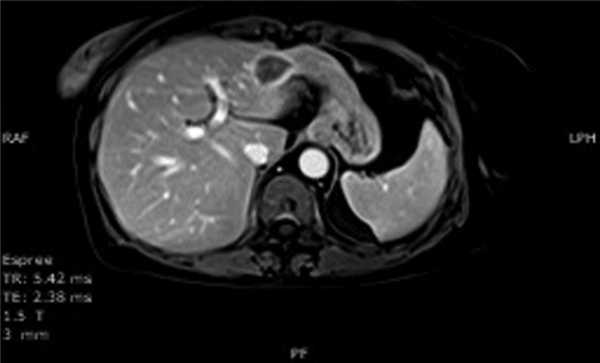

Проведено 8 курсов полихимиотерапии (ПХТ) по схеме R-CHOP + велкейд. По окончании ПХТ в сентябре 2011 г. при рестадировании стадии по данным магнитно-резонансной томографии (МРТ) с контрастированием в печени выявлены 2 очага неоднородной структуры с неровными контурами в III сегменте левой доли размером 33×25×26 мм (рис. 3) и в VI сегменте правой доли размером 30×26×18 мм. Пациентке выполнена резекция II, III и VI сегментов печени. При гистологическом исследовании в ткани печени выявлены инфильтраты из мелких лимфоидных клеток с ядрами неправильной формы (рис. 4, а). Иммуногистохимическое исследование продемонстрировало, что лимфоидные клетки экспрессировали CD2, CD3 (см. рис. 4, б) и CD8, но были негативны при реакциях с CD20, CD79а, PAX5 (см. рис. 4, в). Таким образом, лимфоидный инфильтрат состоял из Т-лимфоцитов. Данных, подтверждающих резидуальную В-клеточную лимфому, не получено. Пациентка находится под нашим наблюдением. В течение 38 месяцев сохраняется полная ремиссия лимфомы.

Рис. 3. Данные МРТ: накопление контрастного вещества по периферии очага в артериальную фазу контрастирования.